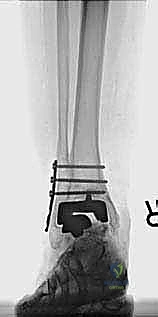

مراجعة مفصل الكاحل الصناعي هي إجراء جراحي ضروري لمعالجة المشاكل التي قد تنشأ بعد الجراحة الأولية، مثل كسور الكعبين أو عدم استقرار المفصل. يتضمن العلاج التشخيص الدقيق عبر الأشعة السينية والتصوير المقطعي، يليه التدخل الجراحي لتثبيت الكسور واستعادة وظيفة الكاحل، مع التركيز على التعافي المبكر.

- الأشعة السينية مع تحميل الوزن (Weight-bearing X-rays): لتقييم الزوايا الميكانيكية وتحديد مدى هبوط المفصل أو وجود كسور في الكعب.

* دمج الكاحل (Ankle Arthrodesis): إذا كان التآكل العظمي هائلاً ولا يسمح بتركيب مفصل جديد، يتم إزالة المفصل الصناعي ودمج عظمة الساق مع عظمة الكاحل باستخدام مسامير وصفائح معدنية وطعوم عظمية.

يتم إدخال المفصل الجديد المخصص للمراجعة، والذي يحتوي غالباً على سيقان (Stems) تدخل عميقاً في عظمة الساق وعظمة الكاحل لضمان الثبات الميكانيكي. في حال وجود كسور في الكعب، يتم تثبيتها في هذه المرحلة.